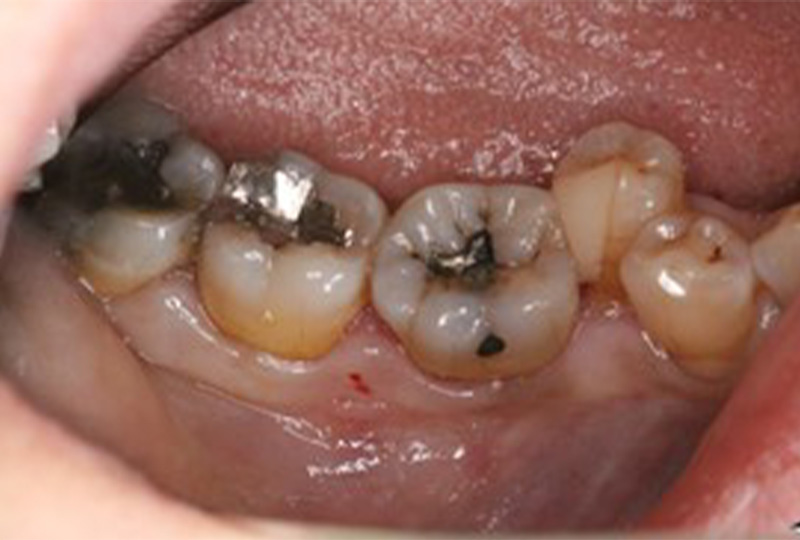

審美性にこだわった治療から保存が難しいと言われた歯の保存やお口全体をより良い状態にする一歩進んだ専門的な治療を行います。

『歯のひび(歯根破折)』など通常であれば抜歯と言われるような歯の保存や歯を失った所に親知らずなどを移動させる『歯の移植』など一般の歯科医院では行わない特殊な治療も行なっております。